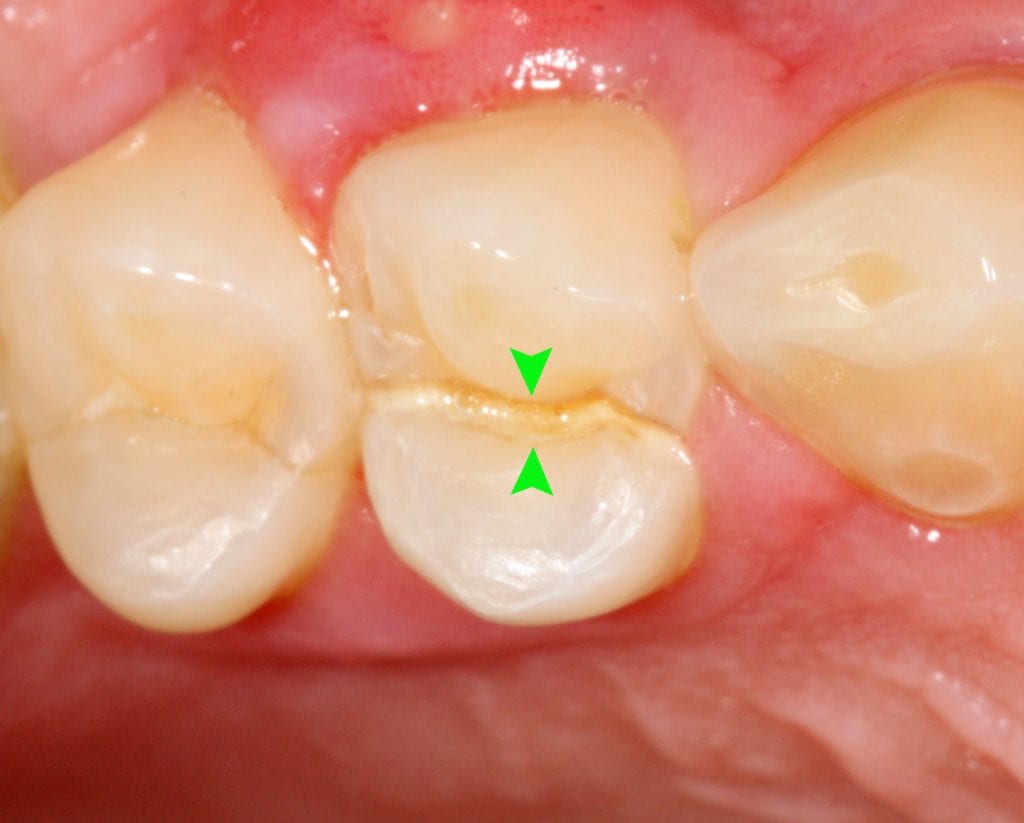

Cracked tooth of the day Dr. Gentry

Crack In Tooth Under Light . Which deeply cracked teeth should be treated and which ones should not? They have a vertical orientation, are straight, and are especially visible if you shine a light on your teeth. If you think you may have a cracked tooth, see a dentist right away because saving a cracked tooth depends on the amount of damage your tooth has experienced and how far the. They aren’t painful, but they can be unsightly. If you bite down on something and feel a sharp, localised pain, it could be a crack opening up under the pressure. And when you release the bite, the crack closes again, causing another jolt of. Craze lines are tiny, hairline cracks on the outside or inside of teeth. Craze lines are small vertical cracks in the enamel of your teeth. Transillumination — shining a bright light through your tooth can help your dentist spot cracks that aren’t obvious on the. A cracked tooth can result from chewing on hard foods, grinding your teeth at night, and can even occur naturally. They may be translucent or can appear yellowish, brown, and gray as they have an increased risk of staining. So, we are left with the question: